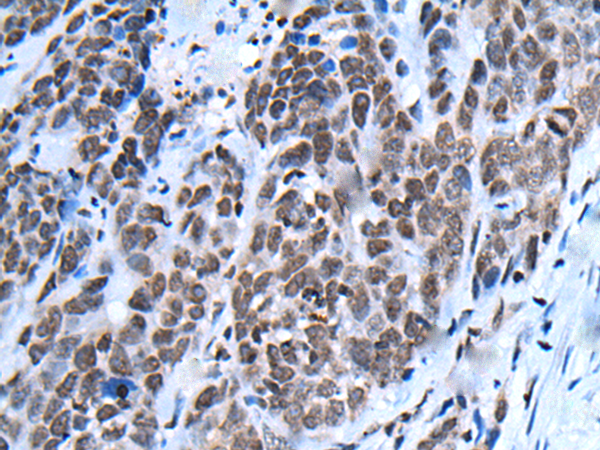

分类: 科研抗体货号: P05945别名: CFND; CFNS; EFB1; EFL3; EPLG2; Elk-L; LERK2应用: IHC反应种属: Human, Mouse, Rat